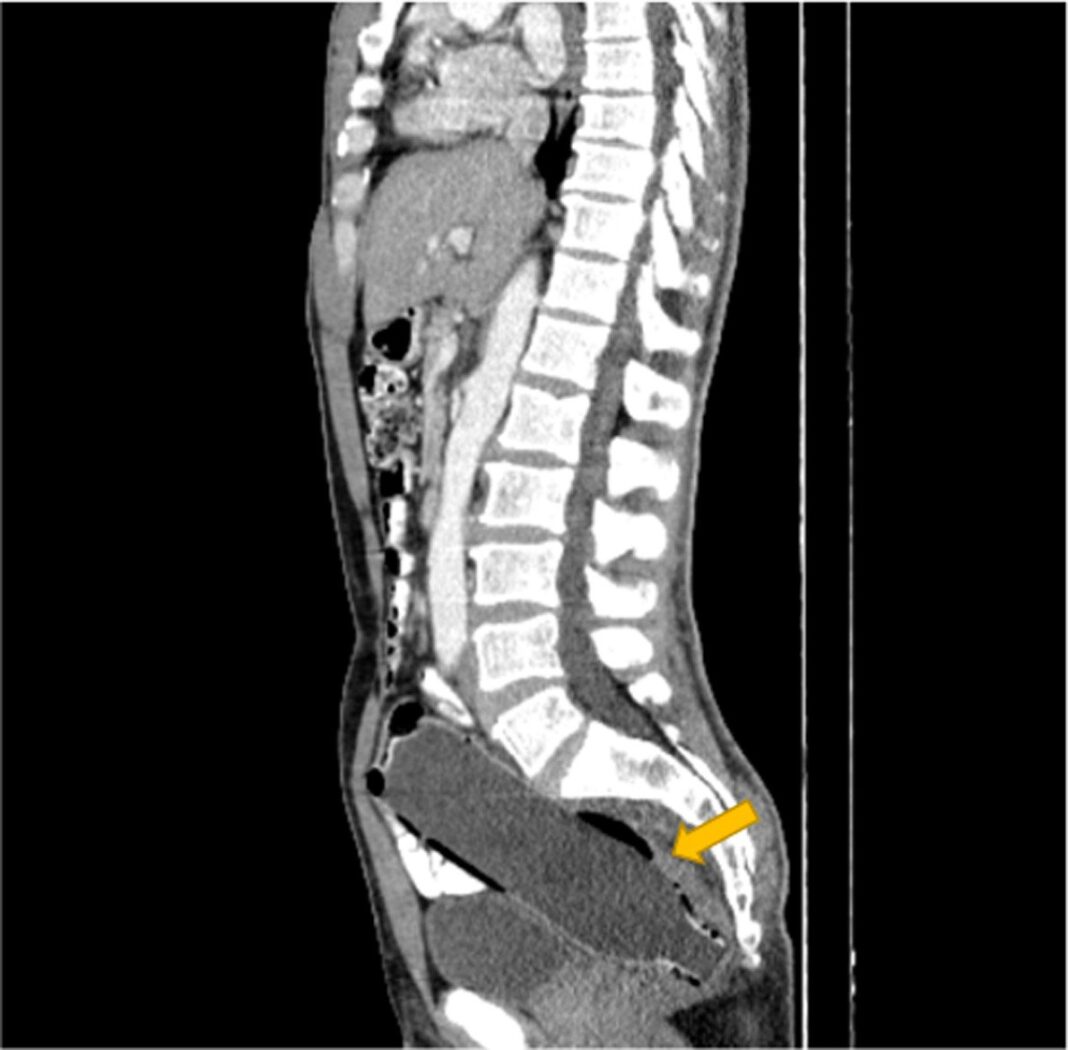

Ο άνδρας συνέχισε να κρύβει με επιτυχία το οδυνηρό μυστικό του, μέχρι που αποκαλύφθηκε στους γιατρούς μέσω αξονικής τομογραφίας.

Σύμφωνα με ένα άρθρο στο Clinical Case Reports Journal, ο άνδρας απέφυγε να αναφέρει ότι είχε τοποθετήσει το αντικείμενο μόνος του, λόγω «αμηχανίας» και «φόβου για τη γυναίκα του».

Η μελέτη αναφέρει ότι είχε εισαγάγει το μπουκάλι με το κάτω μέρος να μπαίνει πρώτο, προκειμένου να χρησιμοποιήσει το επάνω μέρος ως λαβή για να το τραβήξει έξω.

Όταν όμως ήρθε η ώρα να γίνει αυτό, το αντικείμενο παγιδεύτηκε στο παχύ έντερο του άνδρα. Οι γιατροί στο νοσοκομείο Imam Khomeini στο Sari δεν ανέφεραν γιατί ακριβώς το μπουκάλι κόλλησε εκεί, αλλά είπαν ότι η σεξουαλική ικανοποίηση κρύβεται συνήθως πίσω από τέτοιου είδους καταστάσεις. Ο άνδρας ήταν επίσης γνωστό ότι είχε ιστορικό κατάθλιψης, σύμφωνα με το Clinical Case Reports.